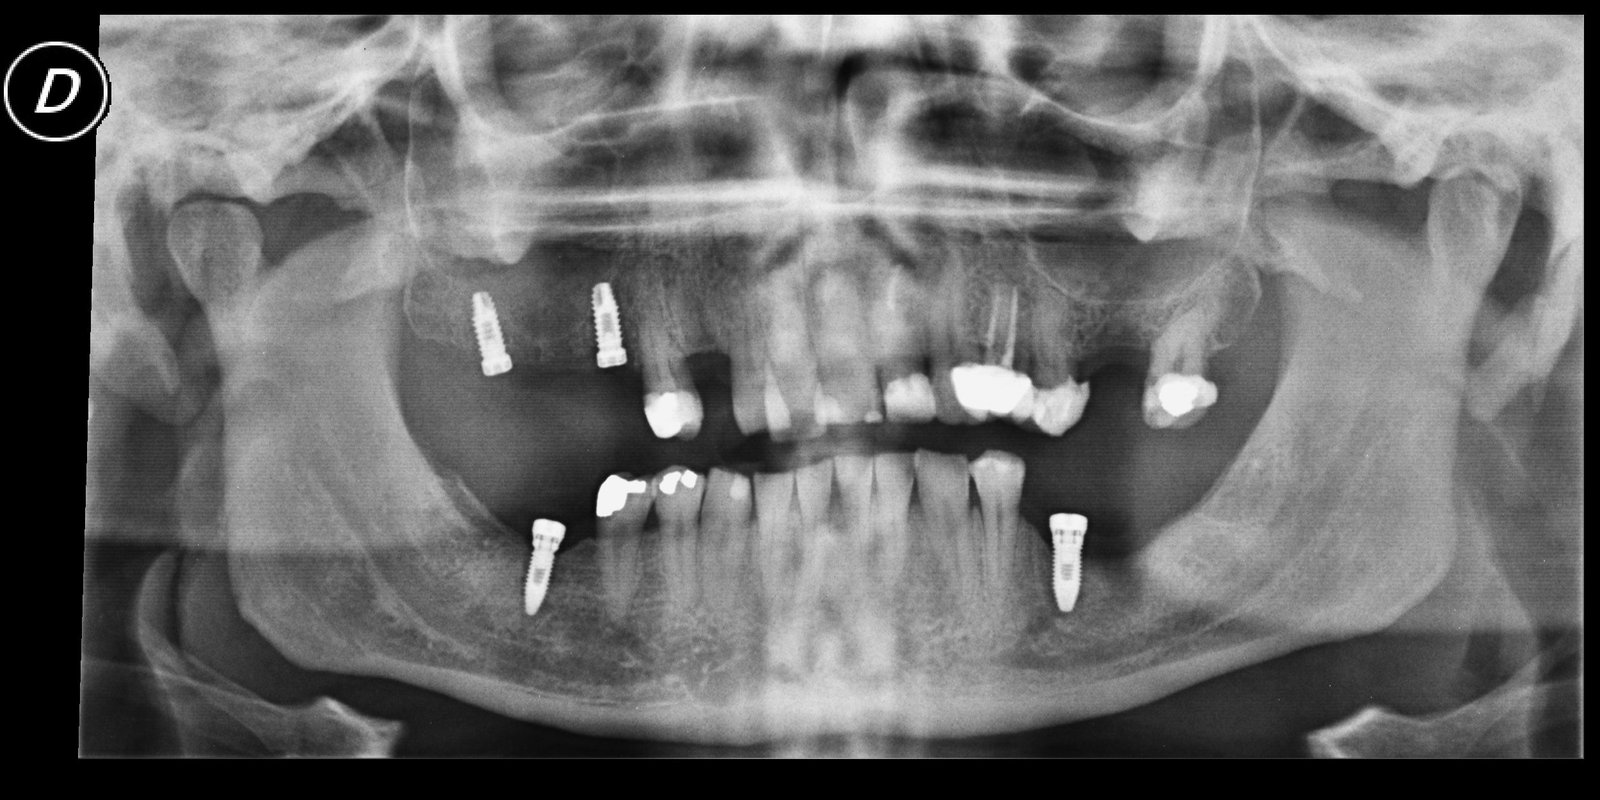

Paciente que viene de Idental. La prótesis superior hay que cambiarla, pero no sé qué implantes lleva. Ahora lleva una provisional atornillada que se le cae. Que aditamentos necesito??? Que [...]

es un caso de idental, que ha cerrado y ha dejado a los pacientes con el trabajo pagado y a la mitad, tengo varios casos y me gustaria saber con [...]